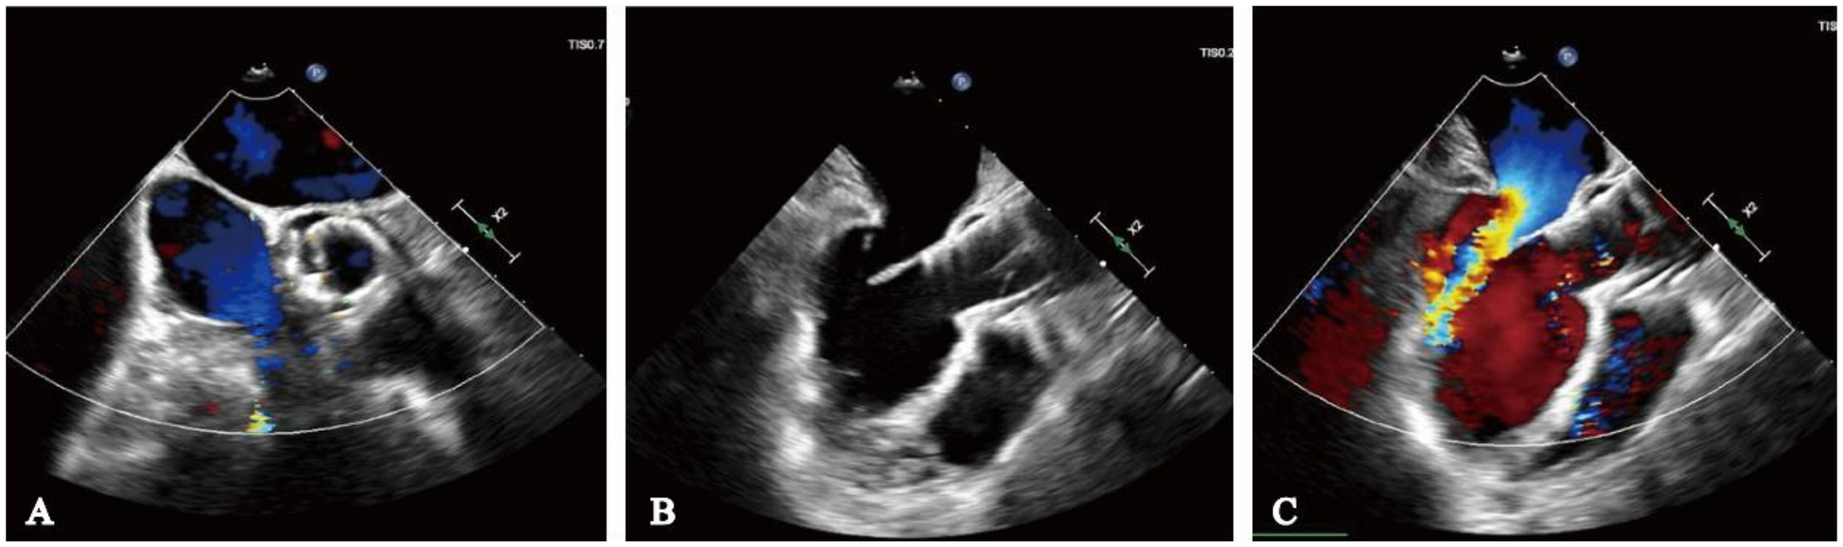

The procedure was successfully performed under general anesthesia in the hybrid operating room via the right femoral artery (Figure 3). LVAD pump speed was maintained at 2,250 rpm, consistent with the preoperative setting. A temporary pacing lead was placed through the left femoral vein, and the left femoral artery was used as secondary access. Under fluoroscopic and echocardiographic guidance, a Taurus Trio-THV 25 valve (28 mm) was implanted via the right femoral artery, with all three locators stably anchored at the sinus base. No rapid pacing was required, and the continuous-flow LVAD did not interfere with valve positioning or deployment. Post-deployment aortography demonstrated only trivial paravalvular leak with patent coronary arteries. Intraoperative transesophageal echocardiography confirmed optimal valve position and morphology, with no paravalvular leak and immediate resolution of aortic regurgitation (Figure 4). Given the patient's long-term warfarin therapy (INR 2–3) due to prior LVAD implantation, the main access site was closed with two ProGlide devices, achieving effective hemostasis, and ultrasound confirmed the absence of bleeding, dissection, or stenosis.

Figure 4

Intraoperative transesophageal echocardiography monitoring. (A) No paravalvular leak on short-axis view; (B) long-axis view indicates adequate valve depth, no impairment of anterior mitral leaflet function; (C) ultrasound color Doppler shows no aortic regurgitation.

Follow-up

At the 1-month follow-up, the patient's symptoms had markedly improved (NYHA functional class II). Transthoracic echocardiography demonstrated normal morphology and function of the prosthetic valve, with no evidence of late prosthesis migration, and spectral Doppler imaging revealed no regurgitation (Figure 5). LVAD parameters remained stable throughout the follow-up period (pump speed 2,200–2,300 rpm, flow approximately 2.5 L/min).

Figure 5

One-month postoperative echocardiographic follow-up. (A) Spectral Doppler showing no evidence of aortic regurgitation; (B) long-axis view demonstrating no late prosthetic valve migration.